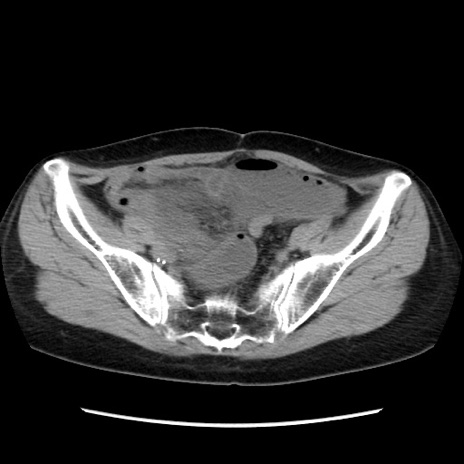

症例32(横断像)

【症例】40歳代 女性

【主訴】上腹部痛、嘔気・嘔吐

【現病歴】約9時間前頃から急に上腹部痛、嘔気、嘔吐が出現。改善しないため救急要請。

【既往歴】子宮頚癌(広汎子宮全摘術、放射線療法)、腸閉塞

【身体所見】腹部:平坦、軟、腸雑音亢進、上腹部を中心に腹部全体に圧痛あり。

【データ】WBC 8400、CRP 0.03